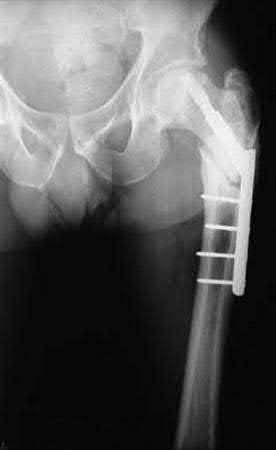

A 64-year-old woman is thrown off a horse, sustaining the injury shown in Figures A and B. She undergoes surgical fixation as seen in Figures C through E. What is the most commonly reported complication of this procedure?

The patient in the scenario has a 2-part proximal humerus fracture treated with a locking plate as seen in Figures A-E. The most common complication with the use of this implant is screw penetration. The terms screw cut out and penetration are often used interchangeably in the literature with cut out appearing more frequently in reports regarding intertrochanteric fractures.

Owsley et al retrospectively reviewed 53 proximal humerus fractures treated with locking plates and the same post-operative protocol. The most common complication was screw cut out or penetration, followed by varus displacement. They concluded that 3 and 4-part fractures in patients over 60 years have a higher incidence of failure.

Agudelo et al retrospectively reviewed 153 patients at a level-one trauma center treated with proximal humerus locking plates, investigating modes of failure for the implant. They determined that varus malreduction (head-shaft angle